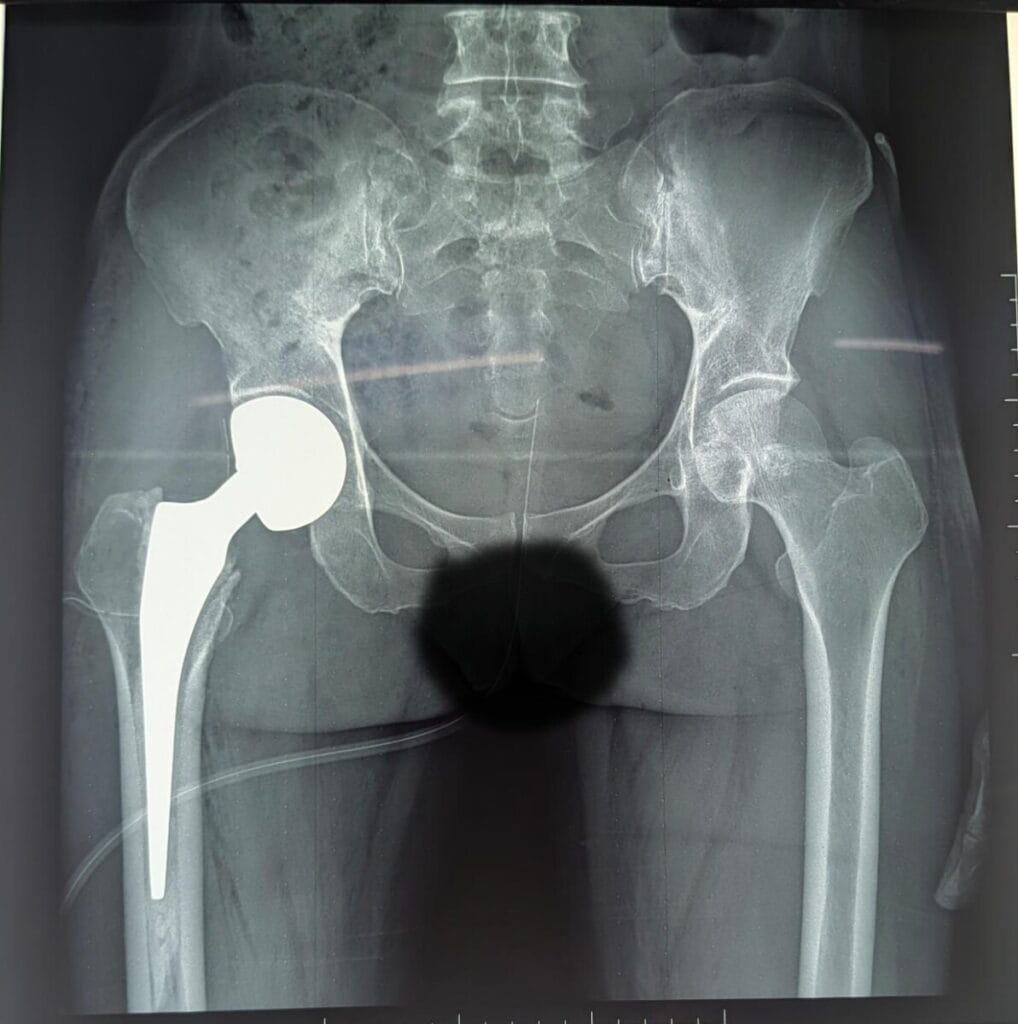

Au CHR Kaya, chaque patient bénéficie d’un suivi attentif et de soins de haute qualité, comme en témoigne le cas récent d’une patiente de 65 ans admise le 05 mars 2026 pour une fracture fermée de la hanche droite, type IV de Garden, survenue il y a un mois. Initialement alitée à domicile, elle a pu bénéficier d’une prothèse intermédiaire totalisable de la hanche droite.

Grâce au renforcement continu de son plateau technique et à l’expertise de l’équipe chirurgicale dirigée par le Dr Ouédraogo Hermann chirurgien orthopédiste traumatologue, des anesthésistes conduites par Dr Lompo Fabrice des soins spécialisés sont de plus en plus disponibles.

Nous notons l’engagement sans failles des collaborateurs infirmiers, médecins généralistes de l’unité du post opéré, du kinésithérapeute ainsi que des Garçons et Filles de salle dévoués qui ont rendu les suites opératoires simples. La patiente a retrouvé sa mobilité et repris la marche dès le lendemain (J1) de son intervention, illustrant parfaitement l’efficacité et la rapidité des soins prodigués.

Ce succès s’inscrit dans une dynamique plus large où plusieurs patients, notamment âgés de 74 et 78 ans, ont retrouvé le sourire après des mois d’alitement prolongé. Le CHR Kaya démontre ainsi sa capacité à redonner mobilité et qualité de vie grâce à une prise en charge personnalisée et un travail d’équipe exemplaire. Cette approche rassure les patients comme leurs familles : ici, chaque jour est une promesse renouvelée d’excellence médicale au service du bien-être.